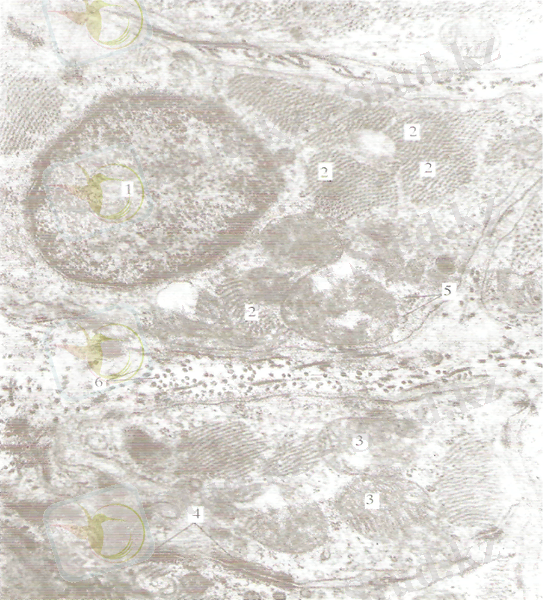

Жүрекше - қарынша будасы (Гис будасы)

1- жиырылғыш кардиомиоциттер; 2- жүрек-ше - қарынша будасының (Гис будасы) өткізгіш кардиомиоциттері; 3-дәнекер тіні; 4-нерв тал-шықтарының будасы (В. Д. Ваколюк препараты) .